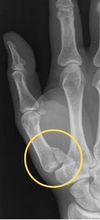

What X-ray changes are seen in psoriatic arthritis? (3)

- may show a combination of erosions and new bone formation - periostitis - 'pencil-in-cup' appearance in advanced disease